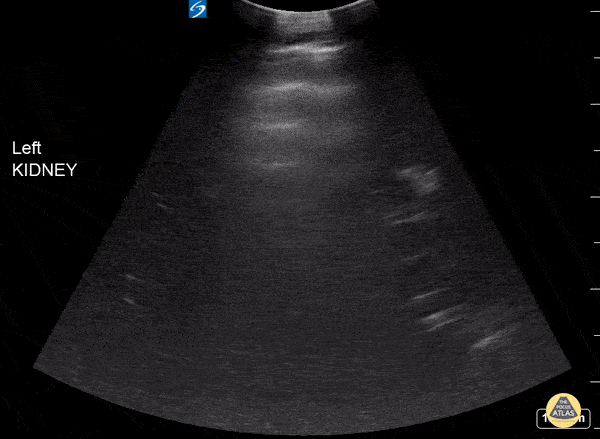

This image of the left upper quadrant of the abdomen shows multiple cystic structures of various sizes surrounding renal pelvis in patient with end stage renal disease on dialysis. This patient has recessive polycystic kidney disease. Please give credit to Dr. Michael Caro, DO, as well. Affiliations: Crozer Chester Medical Center, Upland, PA. Leslie Crosby @LeslieCrosbyMD1